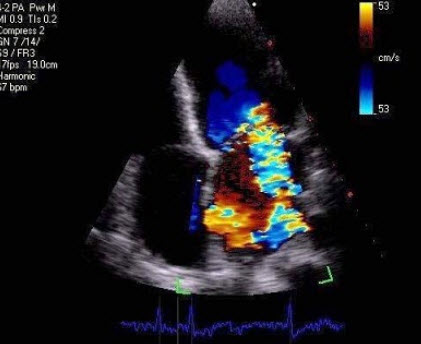

30、单项选择题

根据心尖四腔切面声像图所示,超声诊断为()

A.右房血栓

B.三尖瓣赘生物

C.右房黏液瘤

D.正常声像图

E.二尖瓣脱垂